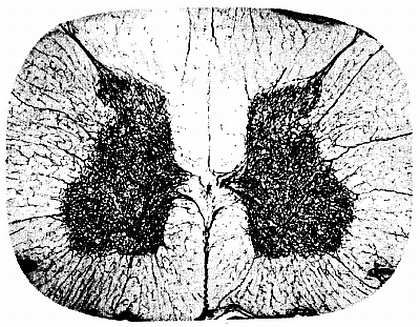

Рис. 271. Сосуды спинного мозга кошки (по И. Д. Льву).